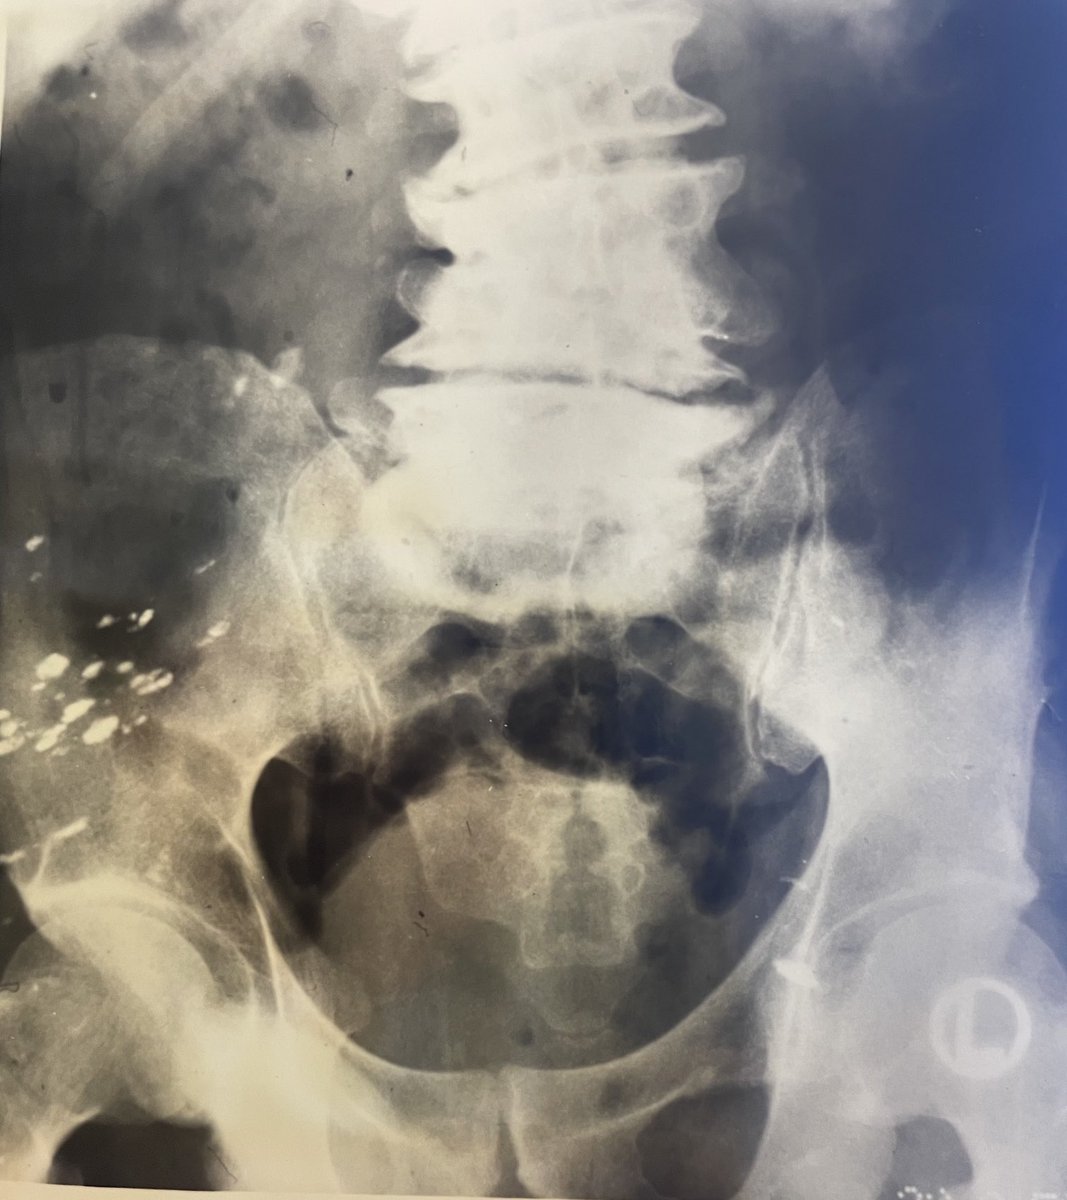

abdominal X-ray from 1950’s showing collapsed vertebrae and radiopaque material in buttock: SYPHILITIC CHARCOTS ARTHROPATHY TREATED WITH BISMUTH! ( pre-penicillin therapy)